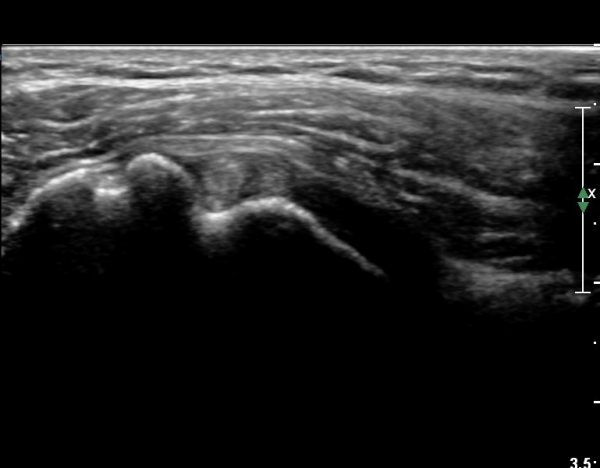

ȸÀü±Ù°³°£°Ý(rotator cuff interval) Ⱦ´Ü¸é°Ë»ç¿¡¼­ ÀÌµÎ¹Ú±Ù°Ç ¿ÜÃø¿¡ ±Ø»ó°ÇÀÌ °üÂûµÇÁö ¾Ê°í

´ë°áÀý Ç¥ÃþÀÇ »À°¡ ¿ïÅüºÒÅüÇÏ°Ô º¯ÇÏ¿´´Ù(±×¸² 1, 2)

ÀÌ´Â ½ÉÇÑ Ãæµ¹ÁõÈıºÀÇ °á°úÀ̰í ȸÀü±Ù°³ ÆÄ¿­À» °­·ÂÈ÷ ¾Ï½ÃÇÏ´Â ¼Ò°ßÀÌ´Ù.